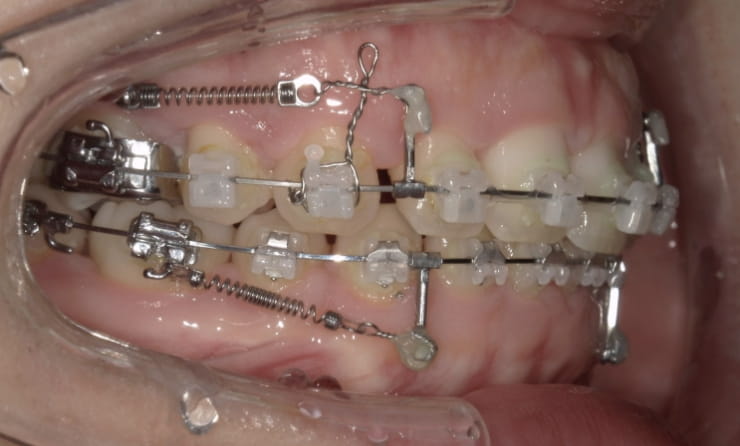

治療装置 上裏側、下表側からのハーフリンガル矯正装置

抜歯 上下4本

治療期間 2年8ヶ月

診断名 歯槽性上下顎前突を伴う叢生

副作用 歯肉退縮・歯根吸収・歯髄壊死・癒着による予期せぬ歯の動き

より綺麗にする希望を達成するために上下4本を抜歯。前歯のリトラクション(後方移動)を行うためにインプラントを使用。若年層ではあるが、インプラントの安定がよく、ヘッドギアに切り替えることなく、順調に進められた。

治療中(19ヶ月後)

治療中(23ヶ月後)